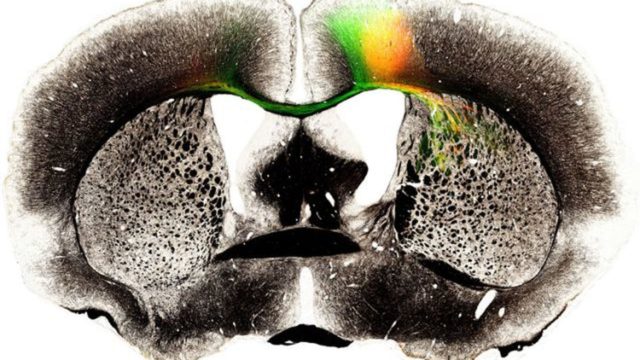

Кажется ученым из Японии удалось найти решение вечного вопроса об оживлении мозга после смерти – правда пока речь идет о мозге мышей. Ученые смогли поддерживать работу мозгу мертвой мыши спустя месяц после ее смерти.

Исследователи использовали специальное устройство, которое поддерживало увлажнение тканей на оптимальном уровне — так, чтобы они не высохли. Ткань получала питательные вещества из влажной среды через полупроницаемый канал, который позволил не нарушить газообмен.

Эксперимент показал, что ткани могут оставаться живыми и поддерживать циркадную активность более 25 дней. На 25-й день мозг сохранил примерно 97% активности, отмечают авторы работы. По словам ученых, их методика поможет улучшить исследования в области органогенеза.